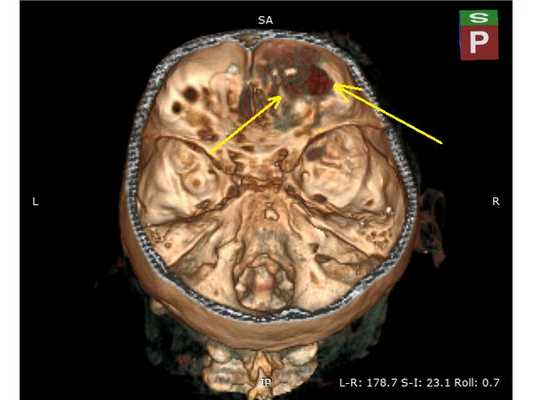

КТ головного мозга на вторые сутки: отсроченное формирование внутримозговой гематомы в правой лобной доле

В связи с отрицательной динамикой неврологического статуса и рентгенологической картины принято решение об оперативном вмешательстве: 1. Удаление внутримозговой гематомы через фрезевое отверстие; 2. Нижняя трахеостомия (для проведения длительной искусственной вентиляции лёшких). Техническая сложность заключалась в широких лобных пазухах пациента, т. к. фрезевое отверстие весьма желательно было наложить, не вскрывая лобную пазуху, но в то же время непосредственно в проекции внутримозговой гематомы. Для этого выполнена предоперационная разметка проекции внутримозговой гематомы на свод черепа. Операция №1 (длительность — 25 минут): ⠀• выполнен 4 см линейный разрез мягких тканей в лобной области справа параллельно естественным морщинам; ⠀• скелетирована кость, произведён гемостаз электрокоагуляцией по ходу доступа, визуализирован линейный перелом лобной кости; ⠀• с помощью краниотома наложено фрезевое отверстие и гемостаз воском; ⠀• твёрдая мозговая оболочка вскрыта крестообразо, визуализирован выход внутримозговой гематомы на кору головного мозга; ⠀• путём аспирации и отмывания физиологическим раствором удалена внутримозговая гематома общим объёмом около 30 мл; ⠀• произведён гемостаз перекисью водорода, дефект твёрдой мозговой оболочки укрыт материалом Surgicell, костная стружка уложена во фрезевое отверстие; Операция №2 (длительность — 15 минут): ⠀• выполнен 3 см линейный вертикальный разрез мягких тканей в проекции трахеи; ⠀• тупым и острым путём обнажена передняя поверхность трахеи и взята на крючок; ⠀• П-образно рассечены два полукольца и заведена трахеостомическая трубка №8.5; ⠀• наложены швы на мягкие ткани, трахеостомическая трубка подшита к коже, наложена асептическая повязка. Всё оперативное вмешательство вместе с анестезиологическим пособием уложилось в 1 час, выполнено с минимальной кровопотерей.

После операции состояние пациента постепенного восстановилось до ясного. На третьи сутки после операции проведена контрольная КТ головного мозга. Также пациент был оперирован по поводу скелетной травмы, деканулирован на восьмые сутки после операции. Операционная рана и трахеостома зажили.

Представленный пример может быть рассмотрен как вариант хирургической тактики при агрессивных очагах ушиба головного мозга. Так, при минимальной хирургической агрессии решены основные проблемы: за один наркоз удалена внутримозговая гематома и выполнена трахеостомия, позволившая освободить полость рта для дальнейшей работы челюстно-лицевого хирурга и проведения продлённой искусственной вентиляции лёгких. Предоперационная 3D-разметка позволила рассчитать доступ — непосредственно в проекции внутримозговой гематомы, но без вскрытия лобной пазухи. Стоит отметить, что удаление травматической внутримозговой гематомы через фрезевое отверстие технически вполне выполнимо, хотя, конечно, обзор весьма ограничен.